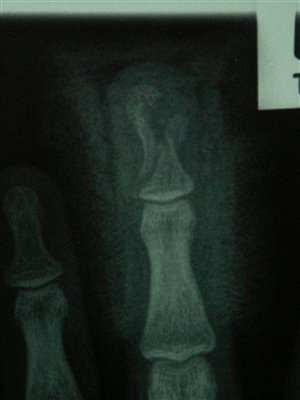

X-ray showing bone break from above. Gap is side of gap in finger